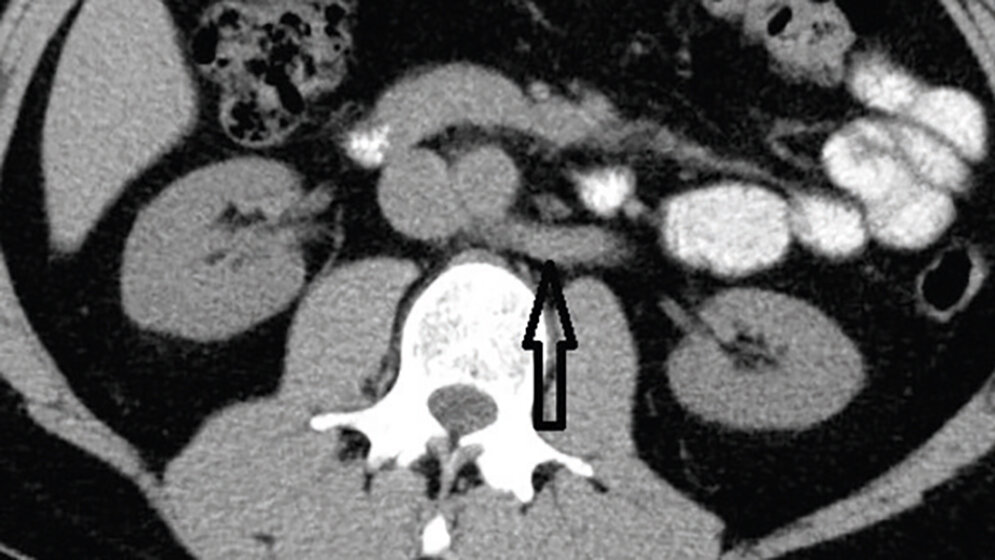

Das Nussknacker-Syndrom ist eine seltene Entität. Symptome wie Flankenschmerz, Hypertension, Hämaturie oder Proteinurie können vorkommen. Das Nussknacker-Syndrom sollte in die Differenzialdiagnose der Hämaturie unklarer Ursache einbezogen werden.

Nutcracker syndrome is a rare entity. Symptoms with flank pain, hypertension, haematuria and proteinuria are possible. Nutcracker syndrome is worth considering especially in differential diagnosis of haematuria of unknown origin.